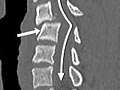

Computed Tomography (CT) Scan of the Spine

Computed Tomography (CT) Scan of the SpineSkip to the navigationTest OverviewA CT scan uses

X-rays to make detailed pictures of the spine and vertebrae. During the

ResultsA computed tomography (CT) scan uses

X-rays to make detailed pictures of the

spine and vertebrae in the neck (cervical spine),

upper back (thoracic spine), or lower back (lumbosacral spine). Complete

results usually are ready for your doctor in 1 to 2 days. CT scan of the spine| Normal: | Spinal bones (vertebrae) are